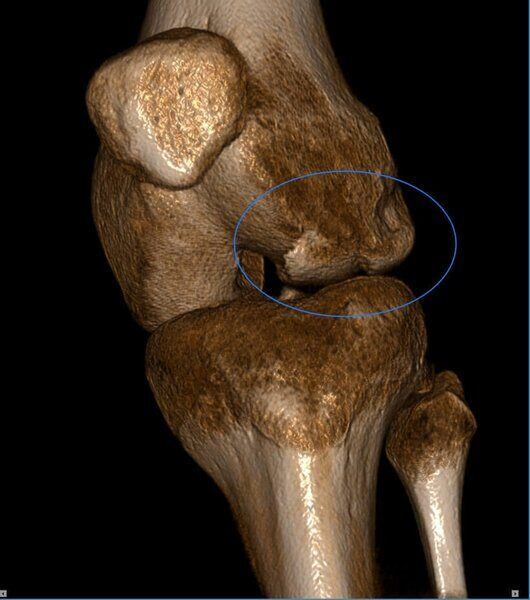

Frattura del Condilo Femorale laterale